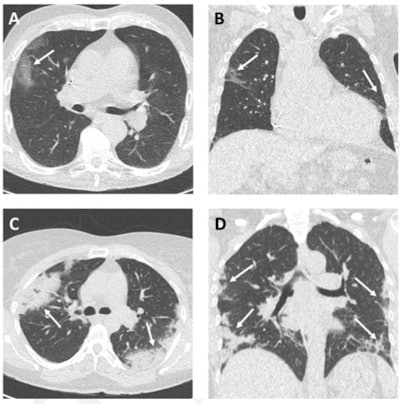

Example CT images in two patients with COVID-19. Axial (A) and coronal (B) CT imaging in an 85-year-old woman presenting with dyspnea and fever for three days. CT shows typical early COVID-19 findings with bilateral subpleural areas of ground-glass opacities (arrows). Effective radiation dose was 0.52 mSv. Axial (C) and coronal (D) CT images in a 41-year-old woman presenting with a cough and fever for 14 days. CT shows typical late COVID-19 findings with multifocal bilateral subpleural areas of consolidation (arrows). Effective radiation dose was 0.53 mSv. Images and caption courtesy of the RSNA.But CT exams can impart radiation dose to patients -- and interpretation of CT images can take time. So how low can CT radiation dose go and still be diagnostic, and how quickly can CT reports be turned around?